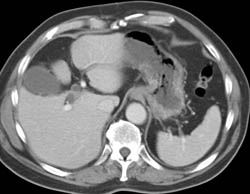

Pancreatic Cancer Obstructs the Common Bile Duct (CBD)